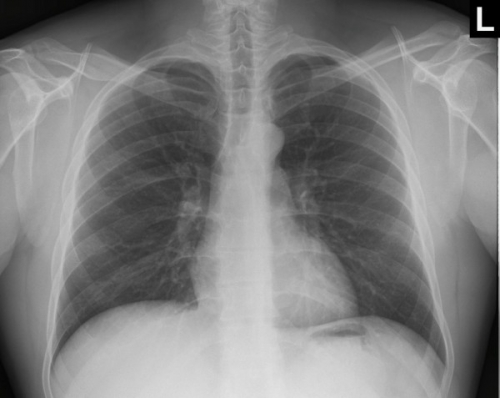

Tool to train medical student's eyes as to what a normal chest x-ray looks like, with over 500 consecutive normal images.